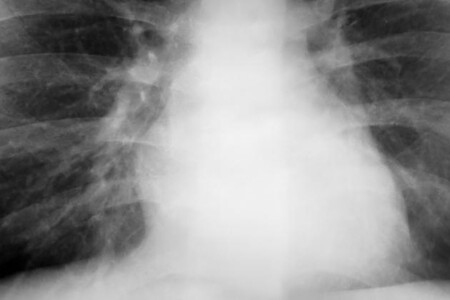

Zvýšený cholesterol v krvi je rizikovým faktorem pro rozvoj aterosklerózy cév, což následně vede ke kardiovaskulárním onemocněním, jako jsou srdeční infarkt, cévní mozková příhoda, plicní embolie anebo ischemická choroba dolních končetin. Velmi významnou roli v léčbě hraje správná životospráva.